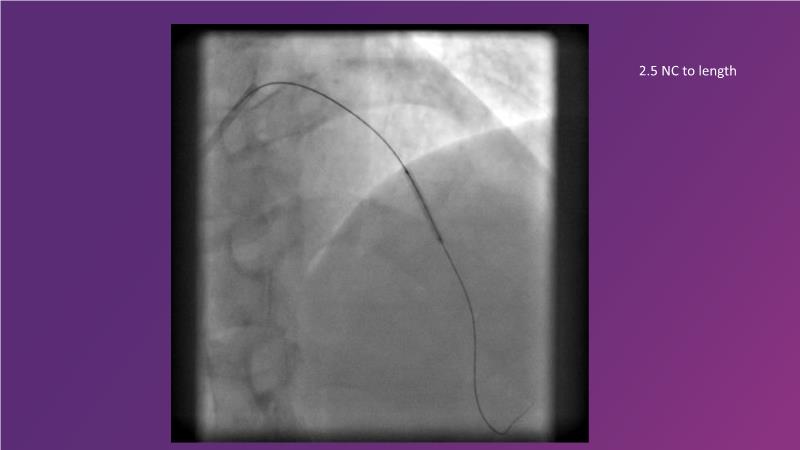

Complex coronary artery disease: can stents and DCB be complementary?

DES and DCB, can these two technologies be complementary for the treatment of the same patient? What are the advantages and how to proceed? You will know everything by watching this presentation based on concrete cases.

- To discuss cases when DCB and DES are complementary